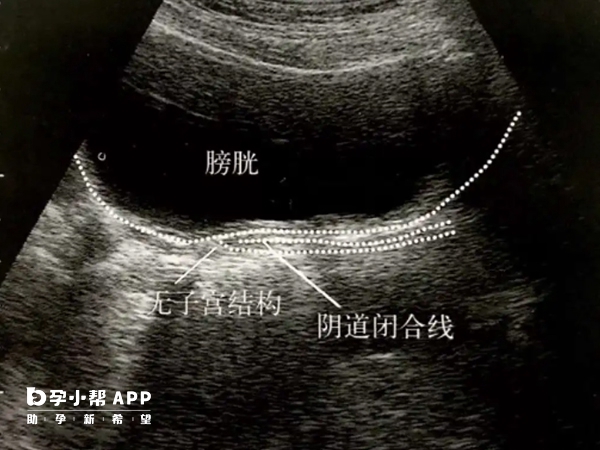

始基子宮多無宮腔和子宮內膜,無月經來潮,常合併無陰道,所以始基子宮型別也分為兩種,一種就是有功能的,一種就是無功能的。像這種無陰道的情況就可以在北京協和醫院做人工陰道成形手術,也可以頂壓法治療,具體可以前往醫院諮詢。